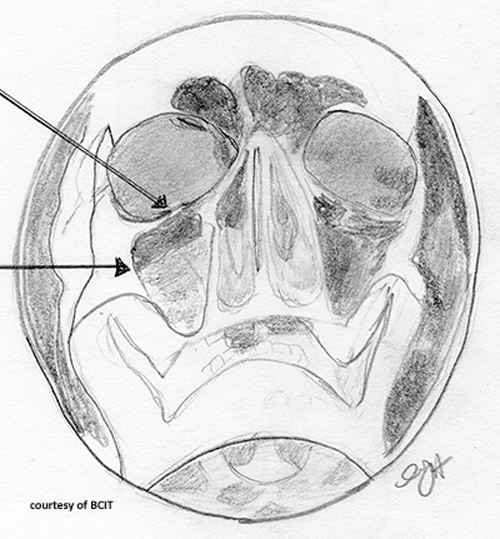

What is a common sign of an inferior orbital rim blow-out fracture?

Tear-drop opacity from trapped orbital muscles.

What is a possible complication of maxilla fracture affecting vision?

Restricted upward eye motion from optic nerve entrapment.